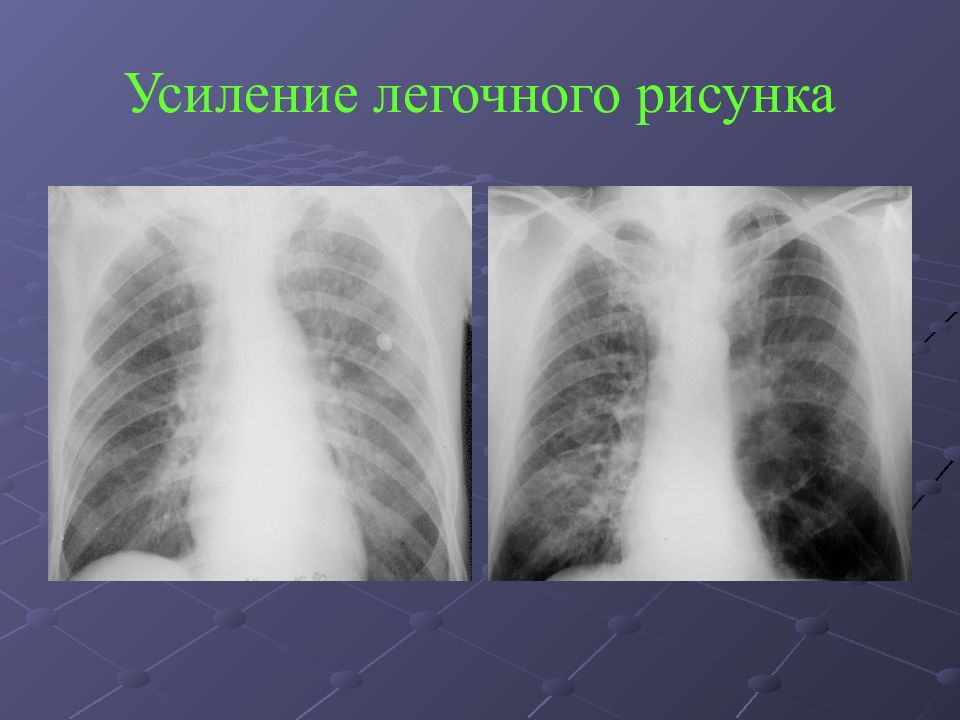

Фотографии, демонстрирующие обнаруженное усиление легочного рисунка

Раздел: Фотодневник открытий